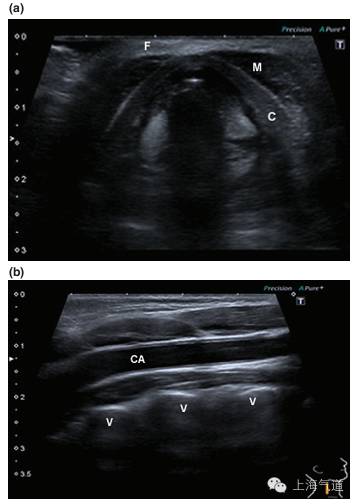

图2a. 将探头置于颏下区取横断面,绿色区域为舌体,红色为口腔内肌肉组织,蓝色为下颌骨及其伪影。b.将探头旋转90度并置于中线位置,取此区域的长轴影像